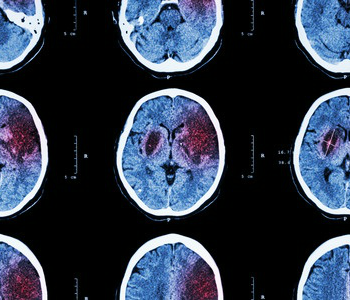

Meta-análise: poluição do ar e AVC

Pergunta Clínica: Existe alguma associação entre a incidência e mortalidade por Acidente Vascular Cerebral (AVC) e a exposição prolongada à poluição atmosférica? Enquadramento: A associação entre poluição atmosférica e doença…